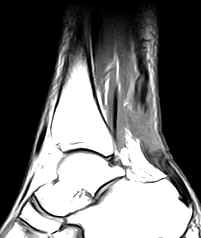

• Complete Rupture:

• There is discontinuity of the tendon (unless the tendon edges are overlapping) with intervening fluid, fat or hemorrhage.

• The proximal fragment is retracted with fraying. The distal fragment is lax and buckled. Sagittal images help in ascertaining the distance between the two fragments.

• Hemorrhage, edema and inflammation may be seen in the peritendinous soft tissues. There may be fluid collection in the paratenon anterior to the tendon.